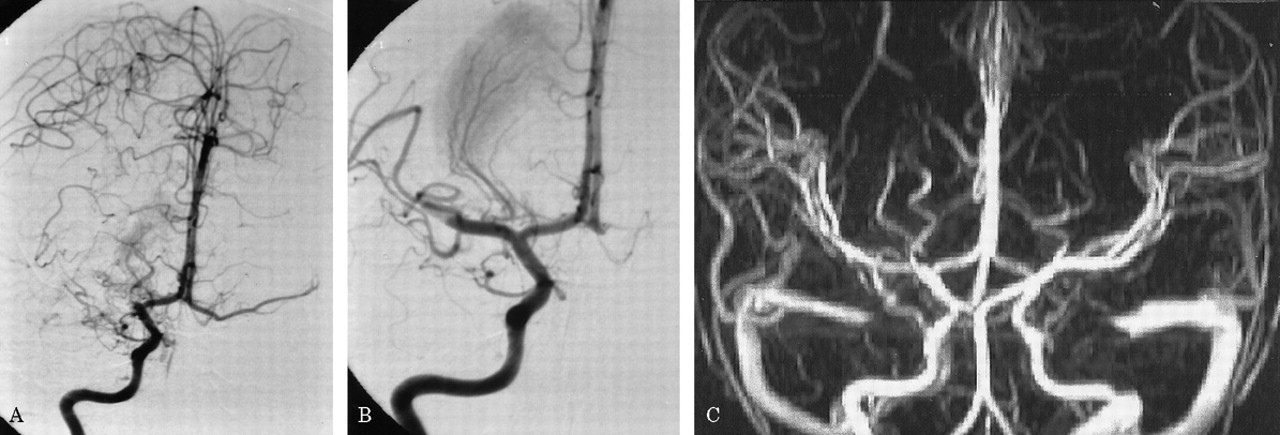

图2。(一)右颈内动脉血管造影披露血栓栓塞大脑中动脉(MCA)阻塞。(B)血管造影在动脉内的溶解(约20分钟后血管造影获得2 a所示)显示了MCA干线的血管再通和纹状体外动脉增外侧。(C) Postinterventional MR血管造影显示血管再通整个MCA的领土。

病人气管切开后的第二天点燃,能够将第二天左胳膊和腿。一周后,这个孩子被动态。点燃了两周后,病人没有残疾在日常生活活动或休闲活动。她经历了一个最小的干扰,同时保持一个较高的位置左胳膊。考试成绩的运动强度(手测功器)和finger-hand协调(手指敲击,将挂钩孔)是在正常范围内。神经心理学评估显示没有语言障碍的迹象,认知或行为。MRI显示一个小纹状体梗死保留内囊(图1 b)。时间进程和振幅的电位诱发外展digiti最小的经颅磁刺激肌肉的皮质是在正常范围内,表示对称完整锥体束功能(延时的左臂,13.8毫秒;延迟的右臂,11.2毫秒)。灌注加权核磁共振没能证明正确的MCA血流动力学妥协领土(图3)。